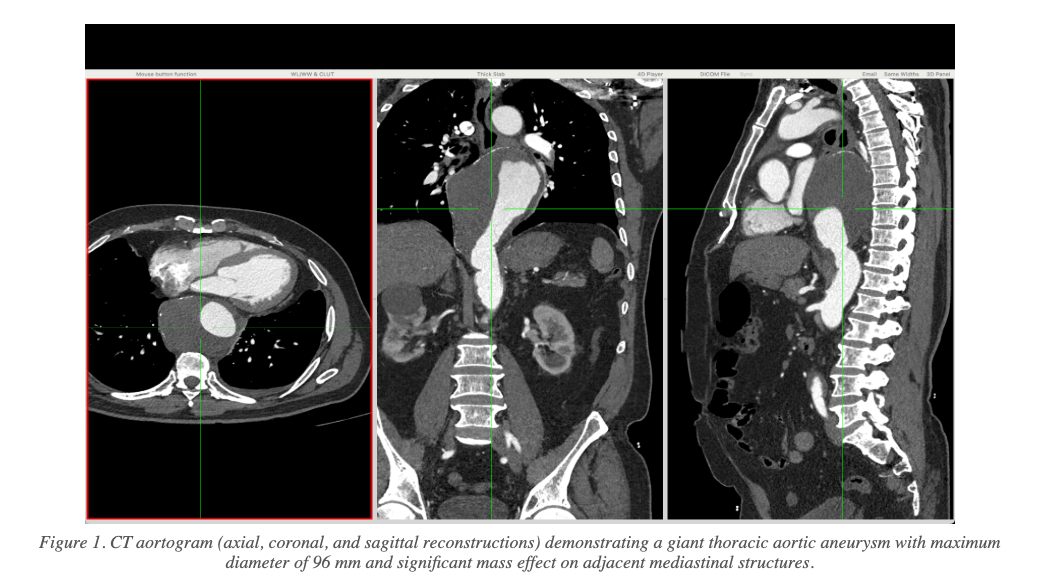

Pre-Procedure CT Findings

CT aortography revealed a giant descending thoracic aortic aneurysm with the following key measurements:

- Maximum aneurysm diameter: 8.3 cm × 9.6 cm

- Significant mass effect on the oesophagus, left atrium, and pulmonary veins

- Adequate proximal landing zone distal to the left subclavian artery (LSCA): 31.8 mm

- Adequate distal landing zone proximal to the coeliac artery: 27.4 mm